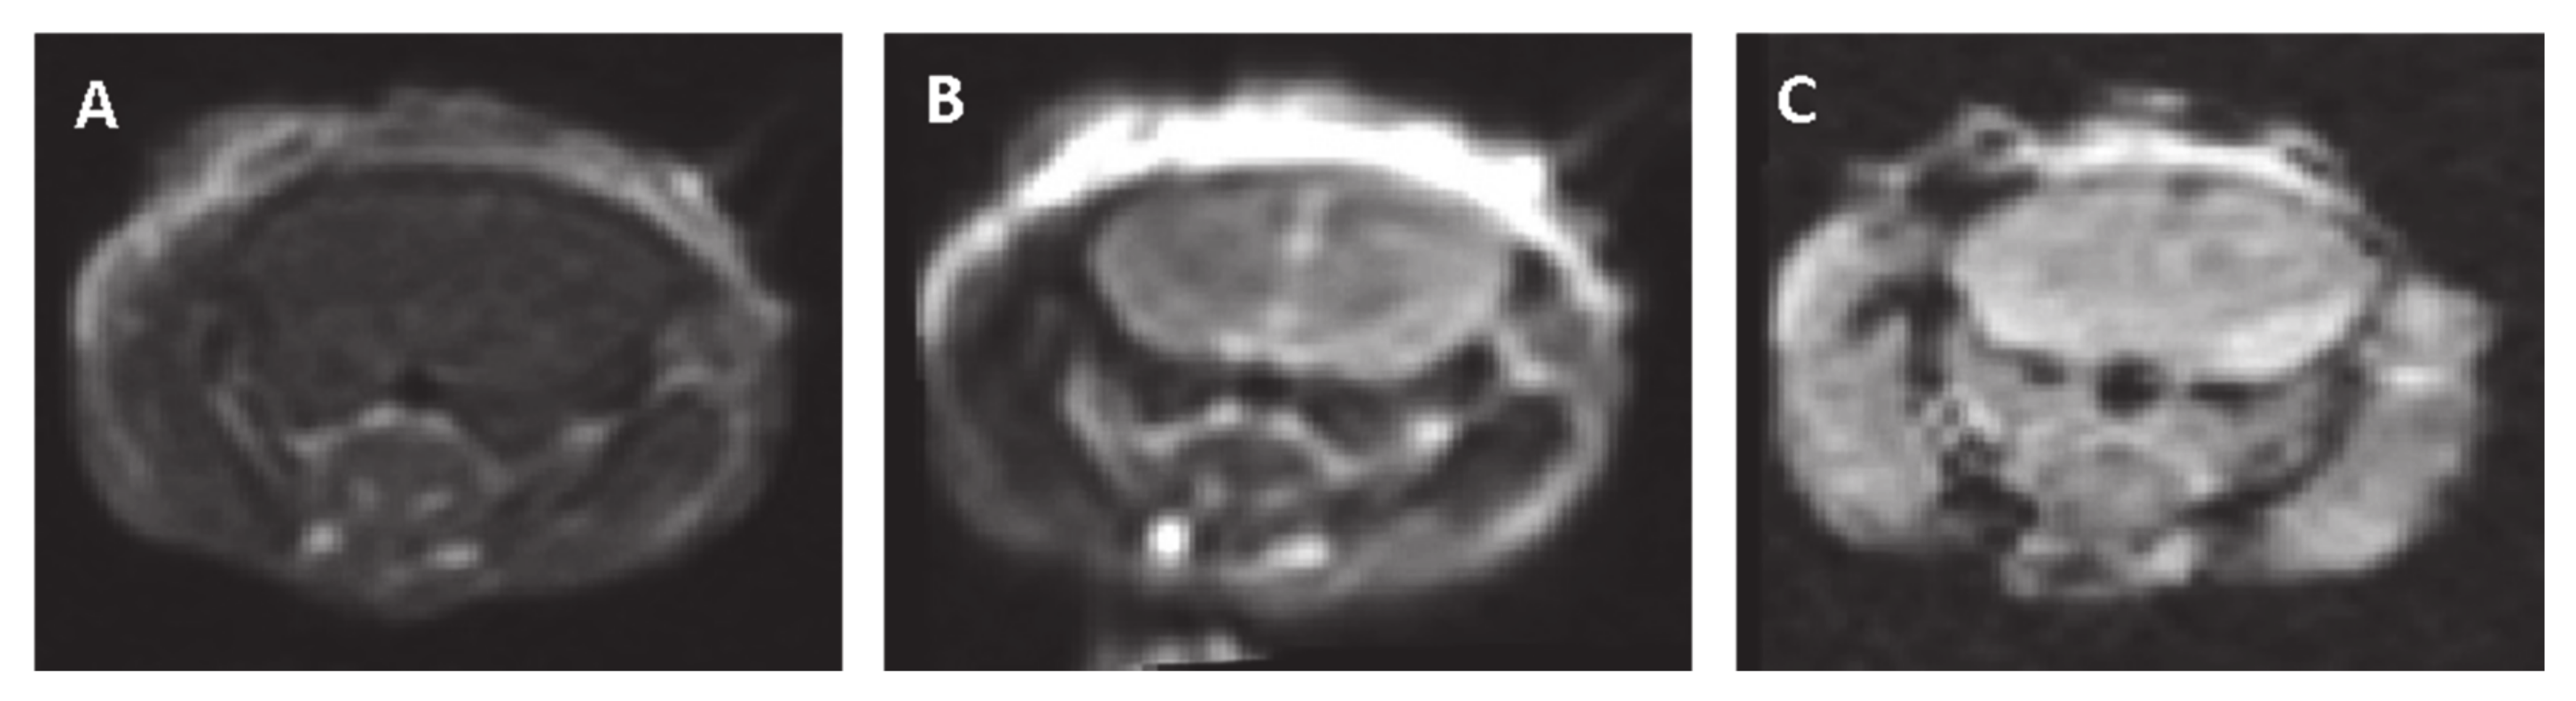

Figure 6.

Representative MRI slices obtained 48 h post-pulsed electrical fields (PEFs) application (100 pulses at 300 V) (A). Contrast-enhanced T1-MRI. (B) T2-MRI. (C) Gradient echo (GE) MRI.

In order to evaluate late treatment effects, six mice underwent MRI 48 h post-treatment. No enhancement was observed on the contrast-enhanced T1- MRIs nor hyper-intense regions on the T2-MRIs that might suggest BBBd, edema or tissue damage. No hypo-intense regions were observed on either the GE images or the SWAN images, suggesting no bleedings occurred. Figure 6 shows representative brain slices of a mouse treated with 100 pulses at 300 V (the highest applied voltage).